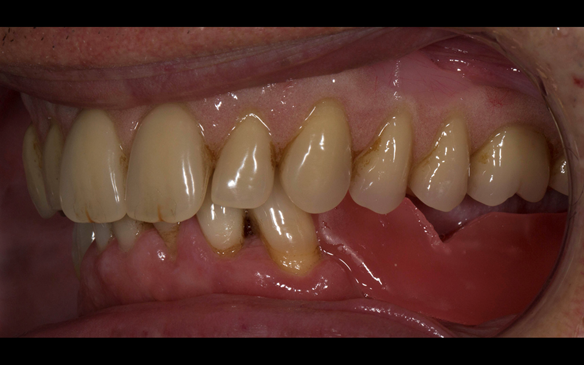

This 52 year old man was referred to me from his general dental practitioner in 2018.

10 years prior to consultation the patient's general dentist diagnosed periodontitis and referred him to Manchester Dental Hospital. He received a treatment plan to manage the periodontitis. Unfortunately, this was not acted on. Four years ago gaps developed between the upper front teeth. Orthodontic treatment was provided to align the teeth. A bonded retainer was fitted onto the upper front teeth. Approximately one year prior to consultation with me the patient noticed the teeth moving again. He consulted his orthodontist, who advised no further orthodontic treatment. One month prior to the consultation with me the upper left central incisor fell out whilst eating.

- Generalised periodontitis; stage IV grade C: currently unstable, risk factors: smoker.

- The remaining maxillary teeth had hopeless prognosis in the short term. They exhibited 80 - 100% alveolar bone loss with increased mobility (Grade 2 - 3).

- The lower right second premolar and lower left first premolar (LR5 LL4) had hopeless prognosis in the short term. They exhibited 80 - 100% alveolar bone loss with grade 3 mobility.

- The remaining mandibular teeth had approximately 30 - 50% alveolar bone loss with grade 1 mobility.